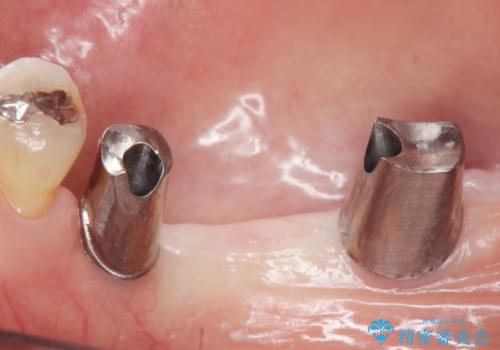

なるべく予算を抑えたいとのご希望から、上顎は入れ歯、右下臼歯部はインプラントによる治療を行いました。

インプラントの種類:スプラインツイスト